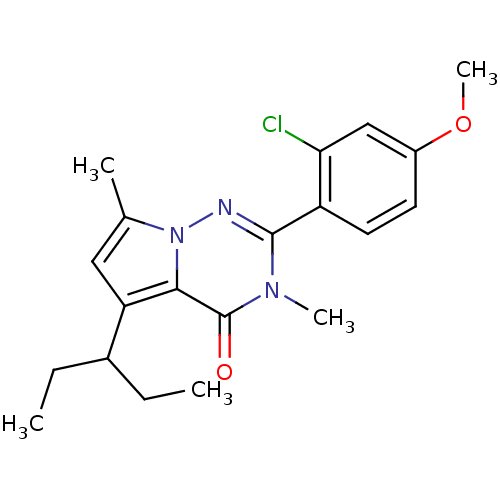

TargetCorticotropin-releasing factor receptor 1(Homo sapiens (Human))

Dupont Pharmaceuticals

Curated by ChEMBL

Dupont Pharmaceuticals

Curated by ChEMBL

Affinity DataEC50: 0.600nMAssay Description:Antagonist activity at human CRF1 receptor expressed in CHO-K1 cells assessed as CRF-stimulated cAMP accumulation by enzyme immunoassayMore data for this Ligand-Target Pair